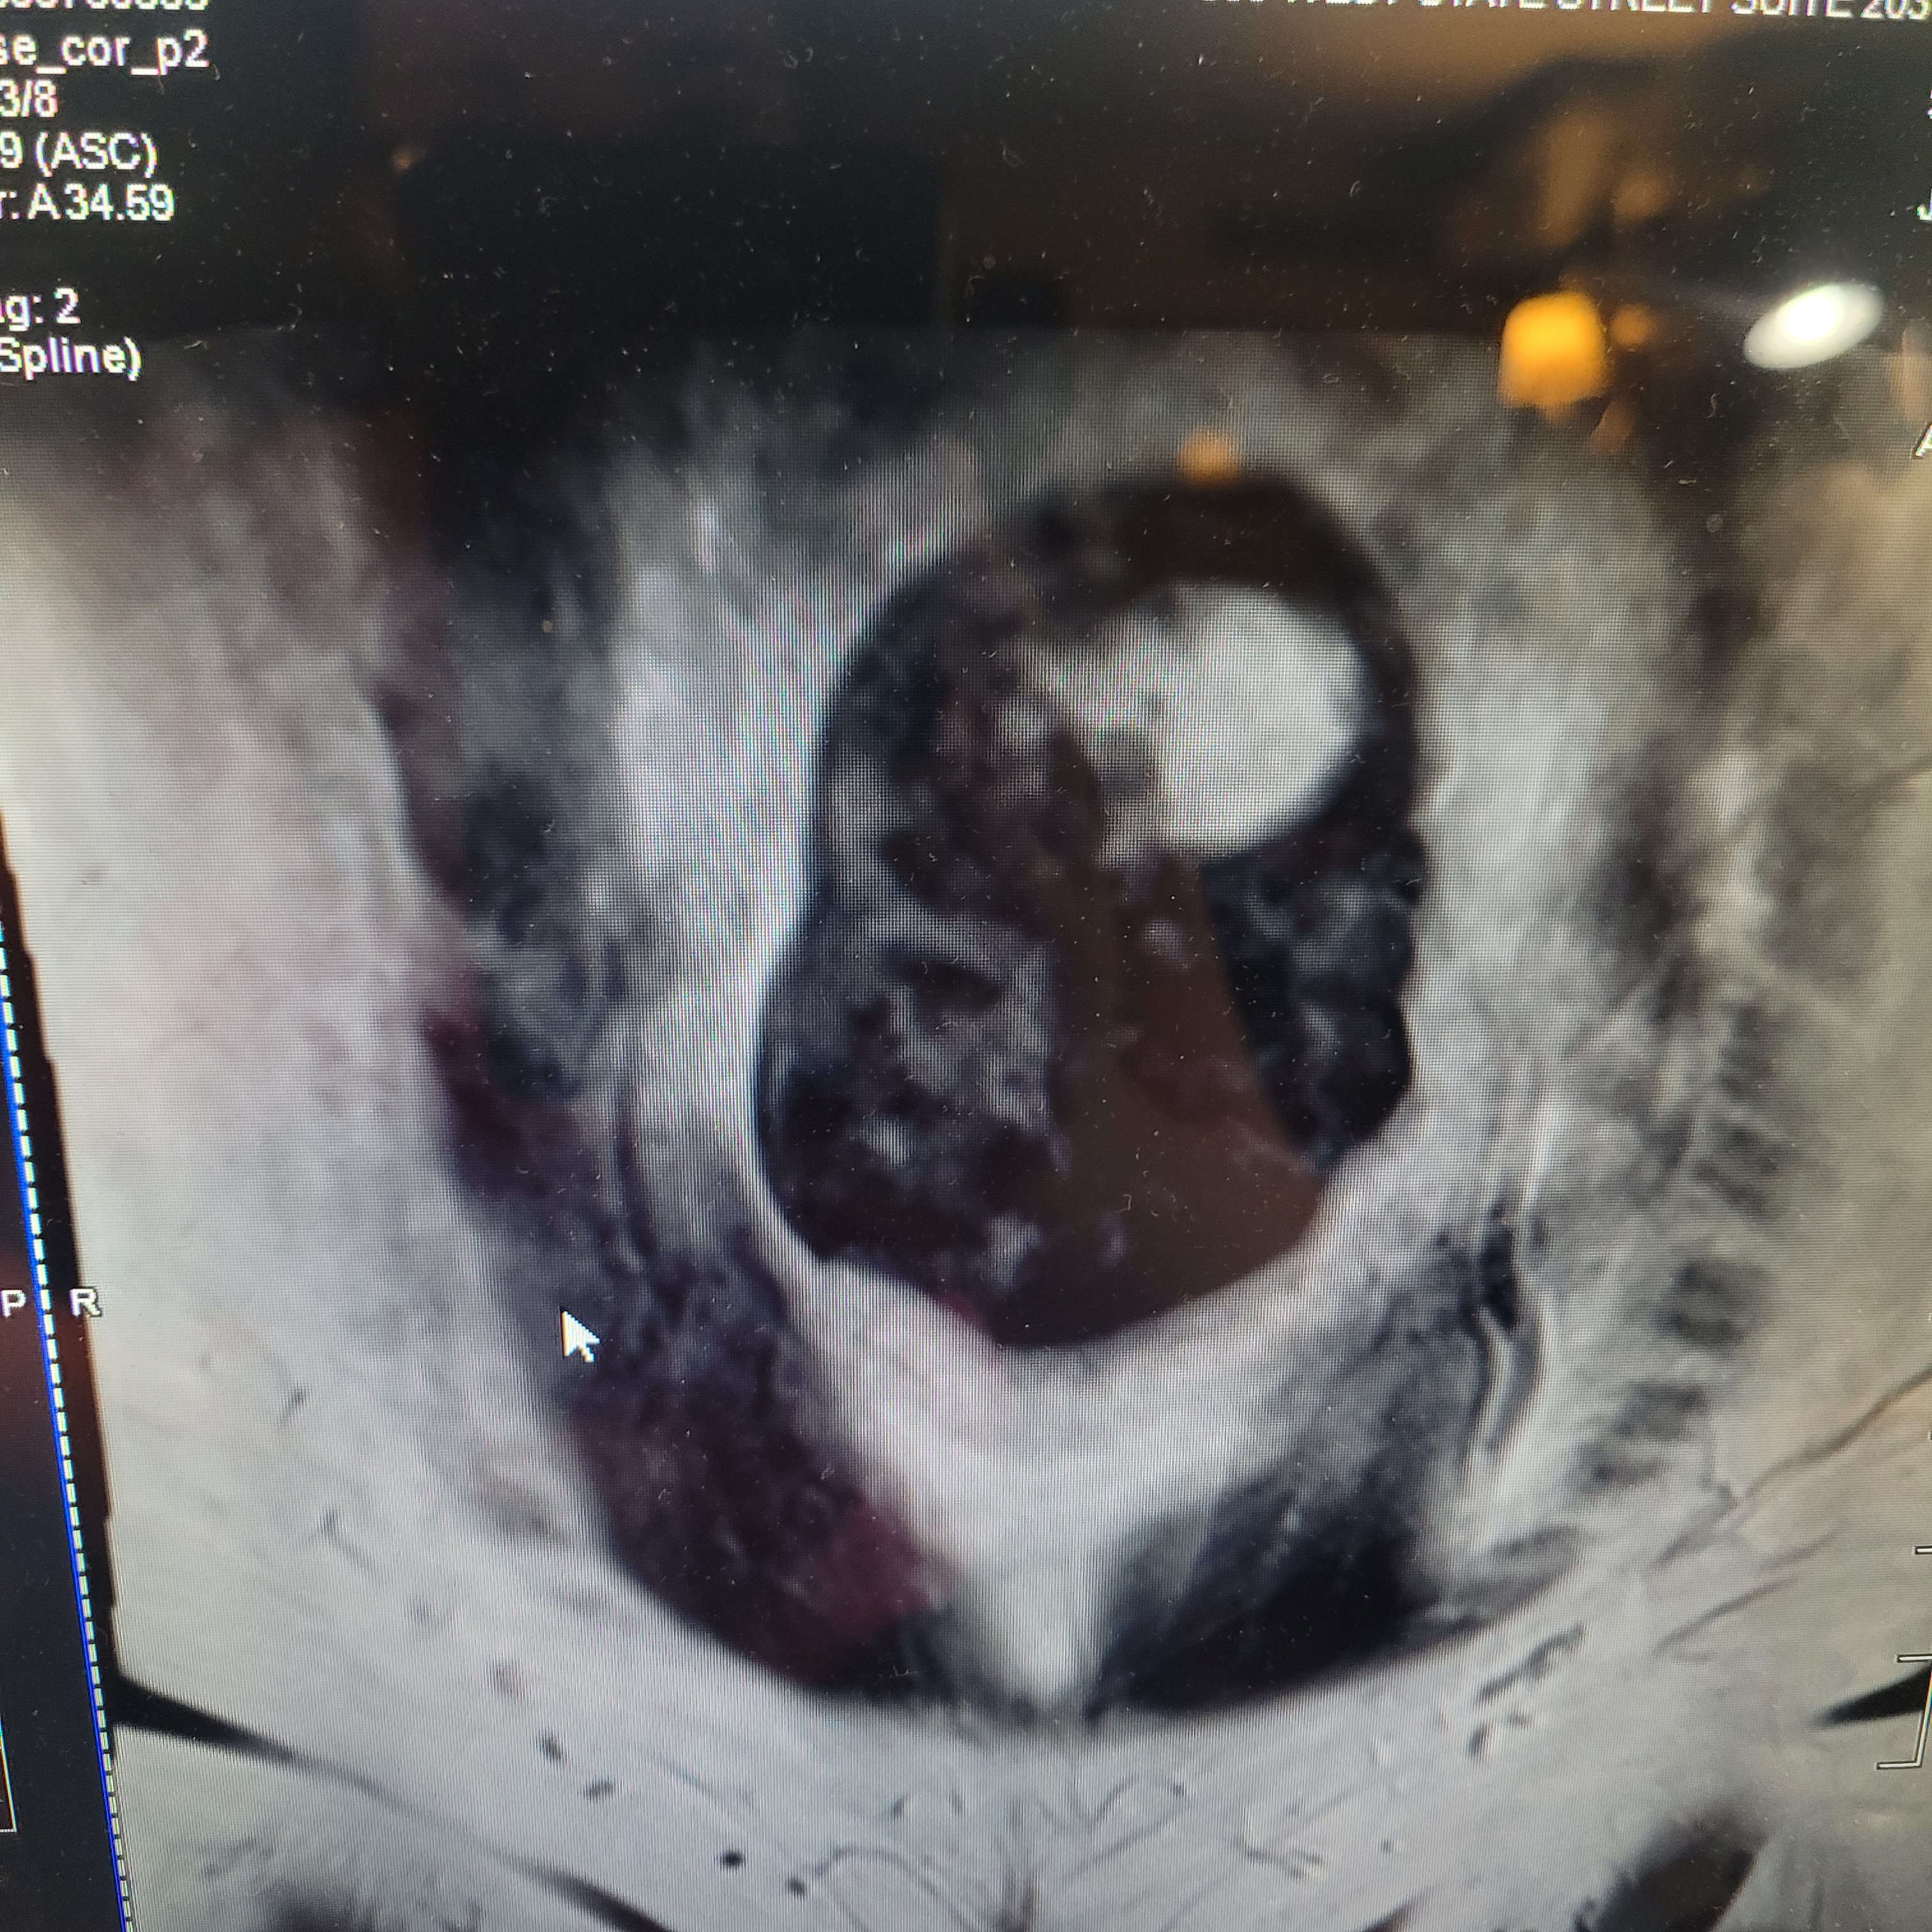

Hi, for those of you who don't know me, my name is Jackie Miller, and I’m a full-time nursing assistant from southeastern Pennsylvania. I have been diagnosed with multiple large uterine fibroids, which are usually noncancerous tumors. However, they won't know for sure until they remove them during surgery and test them. They're located in the uterus and can cause heavy bleeding, pain, and infertility. I am due to get my surgery on August 29th 2025.

I was told that I'm at risk of blood clots due to the pressure they're putting on some important veins in my abdominal area. My doctors have told me to have a myomectomy, which is a surgery to remove the fibroids and preserve my uterus. There are some risks involved and they won't truly know what's going on until they do the surgery.